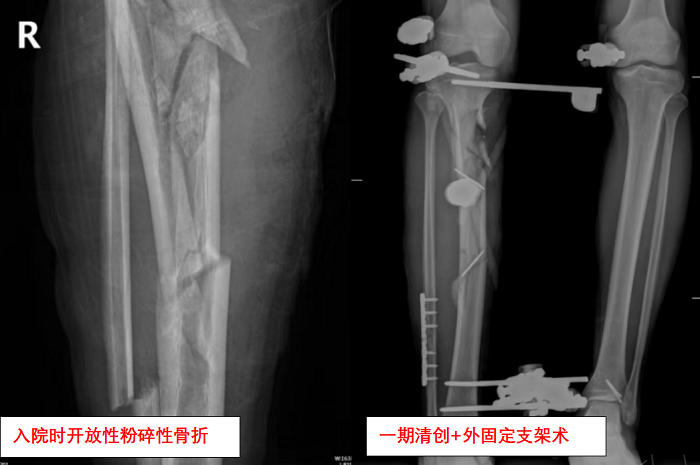

2025-06-19從瀕臨截肢到重新站立!粉碎性骨折后,創(chuàng)傷骨科團隊用七...

? “醫(yī)生,我的腿還能保住嗎?”這是黎先生(化名)被送入急診室時最迫切的問題。? ? 閱讀全文